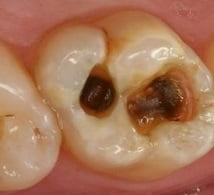

Пульпит зуба: фото

Как выглядит пульпит, на фото представлено поражение зубов при этом заболевании: